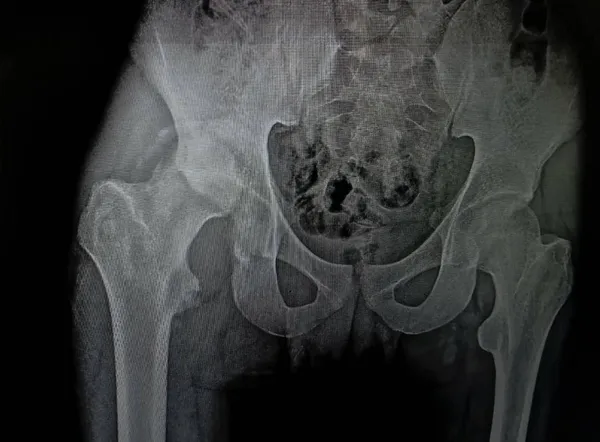

واصل مستشفى كفر الشيخ الجامعي تحقيق إنجازاته المتميزة، حيث نجح فريق قسم جراحة العظام في إجراء عملية جراحية دقيقة ومعقدة تُعد من الحالات النادرة، لمريض كان يعاني من كسر مهمل بالجدار الخلفي للحق الحرقفي مصحوب بخلع مزمن بمفصل الفخذ وتأثر بالعصب الوركي.

وتعود تفاصيل الحالة إلى استقبال المستشفى لمريض يعاني من آلام شديدة بمنطقة الحوض مع سقوط جزئي بالقدم، وذلك بعد مرور شهرين على تعرضه لحادث، وبإجراء الفحوصات والأشعة اللازمة تبين وجود خلع مهمل بمفصل الفخذ مصحوب بكسر في الجدار الخلفي للحق الحرقفي.

وعلى الفور، تم تجهيز الحالة وإدخالها إلى غرفة العمليات، حيث نجح الفريق الطبي في استكشاف وتحرير العصب الوركي، وإجراء رد مفتوح للخلع، وإزالة التعظم بالأنسجة المحيطة، مع إعادة بناء الجدار الخلفي للحق باستخدام رقعة عظمية من داخل عظام الحوض، وتثبيت الكسر باستخدام الشرائح والمسامير، لتكلل العملية بالنجاح ويخرج المريض بحالة مستقرة ونتائج متميزة.